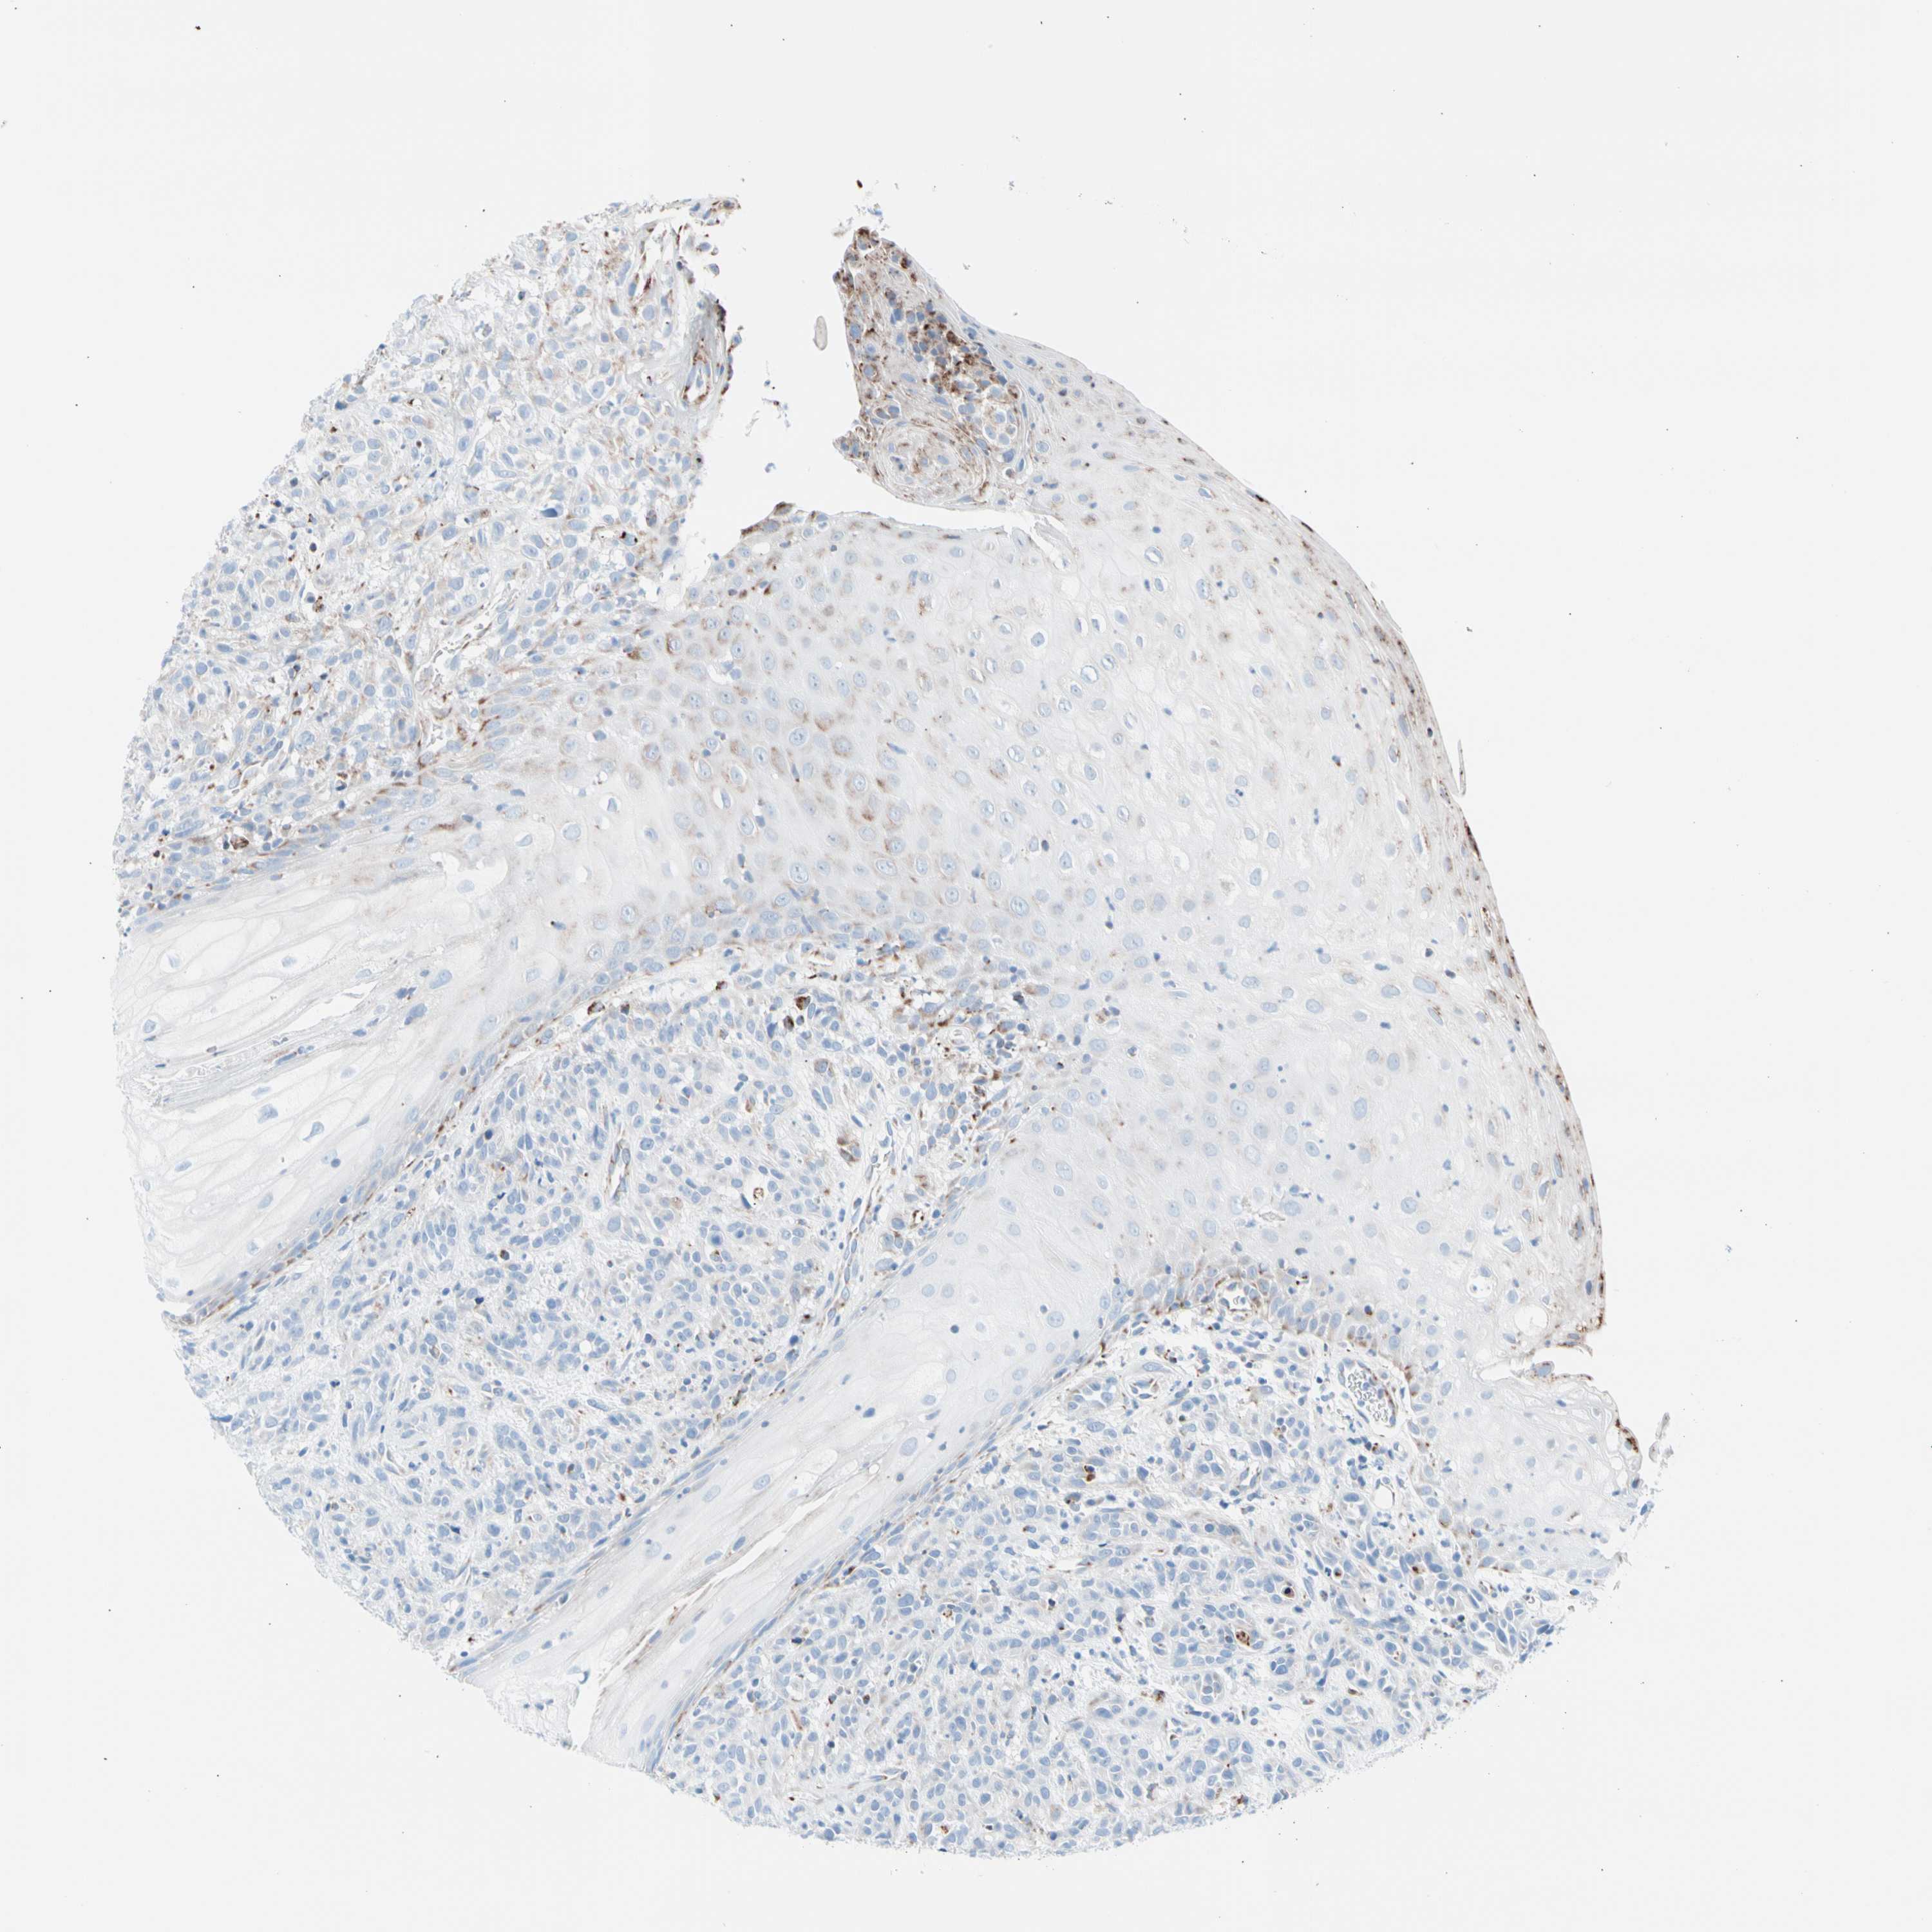

HEAD AND NECK CANCER - Protein expressioni

A mouse-over function shows sample information and annotation data. Click on an image to view it in a full screen mode. Samples can be filtered based on level of antibody staining by selecting one or several of the following categories: high, medium, low and not detected. The assay and annotation is described here.

Antibody stainingi

Antibody staining in the annotated cell types in the current human tissue is reported as not detected, low, medium, or high, based on conventional immunohistochemistry profiling in selected tissues. This score is based on the combination of the staining intensity and fraction of stained cells.

Each image is clickable and will lead to virtual microscopy that enables deeper exploration of all samples and also displays staining intensity scores, fraction scores and subcellular localization as well as patient and tissue information for each sample.

Antibody HPA007043

Antibody HPA007044

Antibody CAB010052

Staining

High

Medium

Low

Not detected

Squamous cell carcinoma, NOS

Adenocarcinoma, NOS

Adenoma, NOS

Squamous cell carcinoma, metastatic, NOS